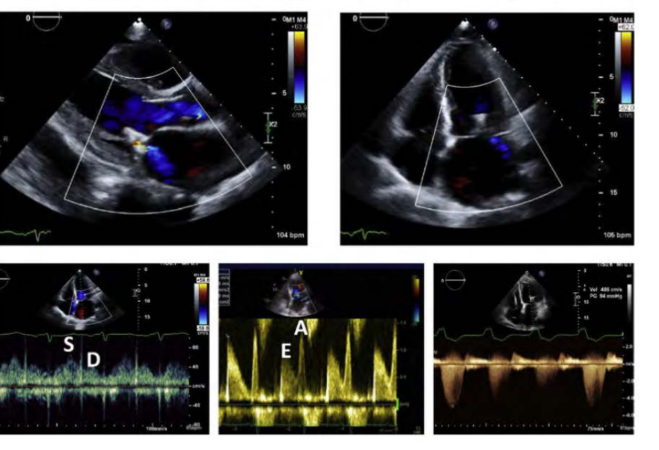

Prosthetic Mitral Valves

Comprehessive evaluation of the mitral valve prothestis includes: name 8

heart rate

peak early velocity ( E- wave )

Mean gradient

PHT

Presence or absence of significant regurgitation

LV, right ventricular (RV), and left atrial size

Estimation of PA pressure and right atrial (RA) pressure

EOA and DVI

Spectral Doppler is key for evaluation of Mitral Prosthesis Regurgitation, name 7 things

what is the CW MR jet look like

How is the mitral E velocity

how is the systemic output and VTI LVOT despite a Hyperdynamic LV

how is the VTI PrMV/VTI Ratio

a large zone of what seen on the LV sie of the mitral prosthesis ****

a what in pressure compared with previous study

flow of the pulmonary veins

the shape changes from a trigu;nar shape to what

Dense CW MR jet

Elevation of the mitral E velocity (>1.9 m/sec in mechanical valves)

Low systemic output and VTI LVOT despite a hyperdynamic left ventricle

An elevated VTI PrMV/VTI LVOT ratio (>2.5)

A large zone of systolic flow convergence seen on the LV side of the mitral prosthesis

A significant rise in the PA pressure compared with a previous study

Reversal of flow in the pulmonary veins (signifcant MR)

to u shape